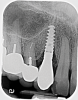

Based on clinical and radiographic examination of the area, the patient was diagnosed with moderate peri-implantitis subcategory A (Figure 10 and Figure 11).19 Pocket depths at this implant ranged up to 9 mm. A surgical approach was planned that included implantoplasty and guided bone regeneration.

Fig 11. Pretreatment radiograph demonstrating bone loss on the mandibular right first molar.

Figure 11